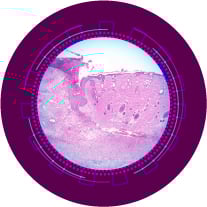

We study how skin diseases and body's responses to skin disorders can be better understood and treated, so as to develop innovative therapies.

Being based in Singapore, we focus on skin conditions that are common in Asia - acne, atopic dermatitis, pigmentary disorders, chronic wounds, and signs of aging.